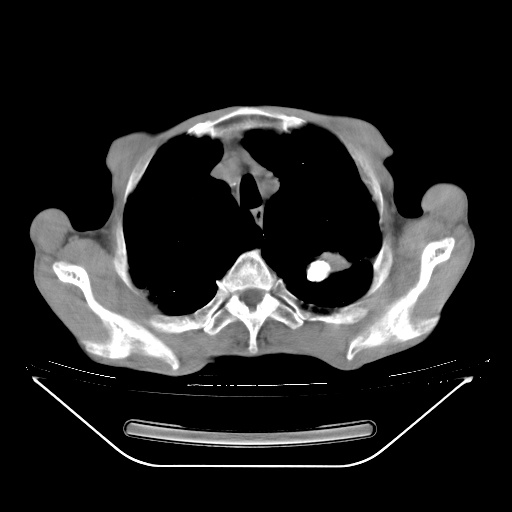

以下是引用zsl6918在2008-8-25 21:55:00的发言:[br]符合右肺周围性肺癌并肺内转移,左肺结核球。双肺肺气肿。腰椎附件转移。

以下是引用随光逐影在2008-8-25 22:03:00的发言:[br]1)考虑右肺下叶周围性肺癌并肺内转移,腰椎附件转移。2)左上肺结核(结核球形成)。3)双肺肺气肿(多发肺大泡形成)。4)双肺门区及纵隔内多发淋巴结钙化。